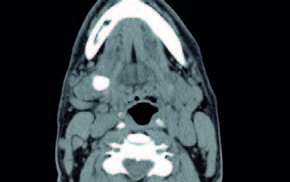

Se presentan unas imágenes de un paciente varón de 55 años, sin alergias conocidas, exfumador desde hace unos pocos años, que consulta por urgencias por inflamación brusca submandibular derecha dolorosa, tiene antecedentes de 5 episodios de submaxilitis derecha por cálculo salivar, desde hace 5 años. En la exploración de la salida sublingual del conducto de Warton se aprecia salida de saliva con supuración. Después de tratamiento antibiótico durante una semana, mejora la inflamación, saliendo saliva clara normal, quedando una hipertrofia de la glándula (figura 4).

La TAC del cuello señala una litiasis submaxilar derecha: ligero aumento del tamaño de la glándula submaxilar derecha observándose en su interior calcificación de 19 x 15 x 15 mm y otras dos pequeñas adyacentes (de 4 y 5 mm respectivamente). No se observan colecciones a nivel de la glándula submaxilar. No se observan otros hallazgos a nivel de laringe o faringe. Sin imágenes ganglionares de tamaño significativo a nivel de las cadenas ganglionares cervicales.